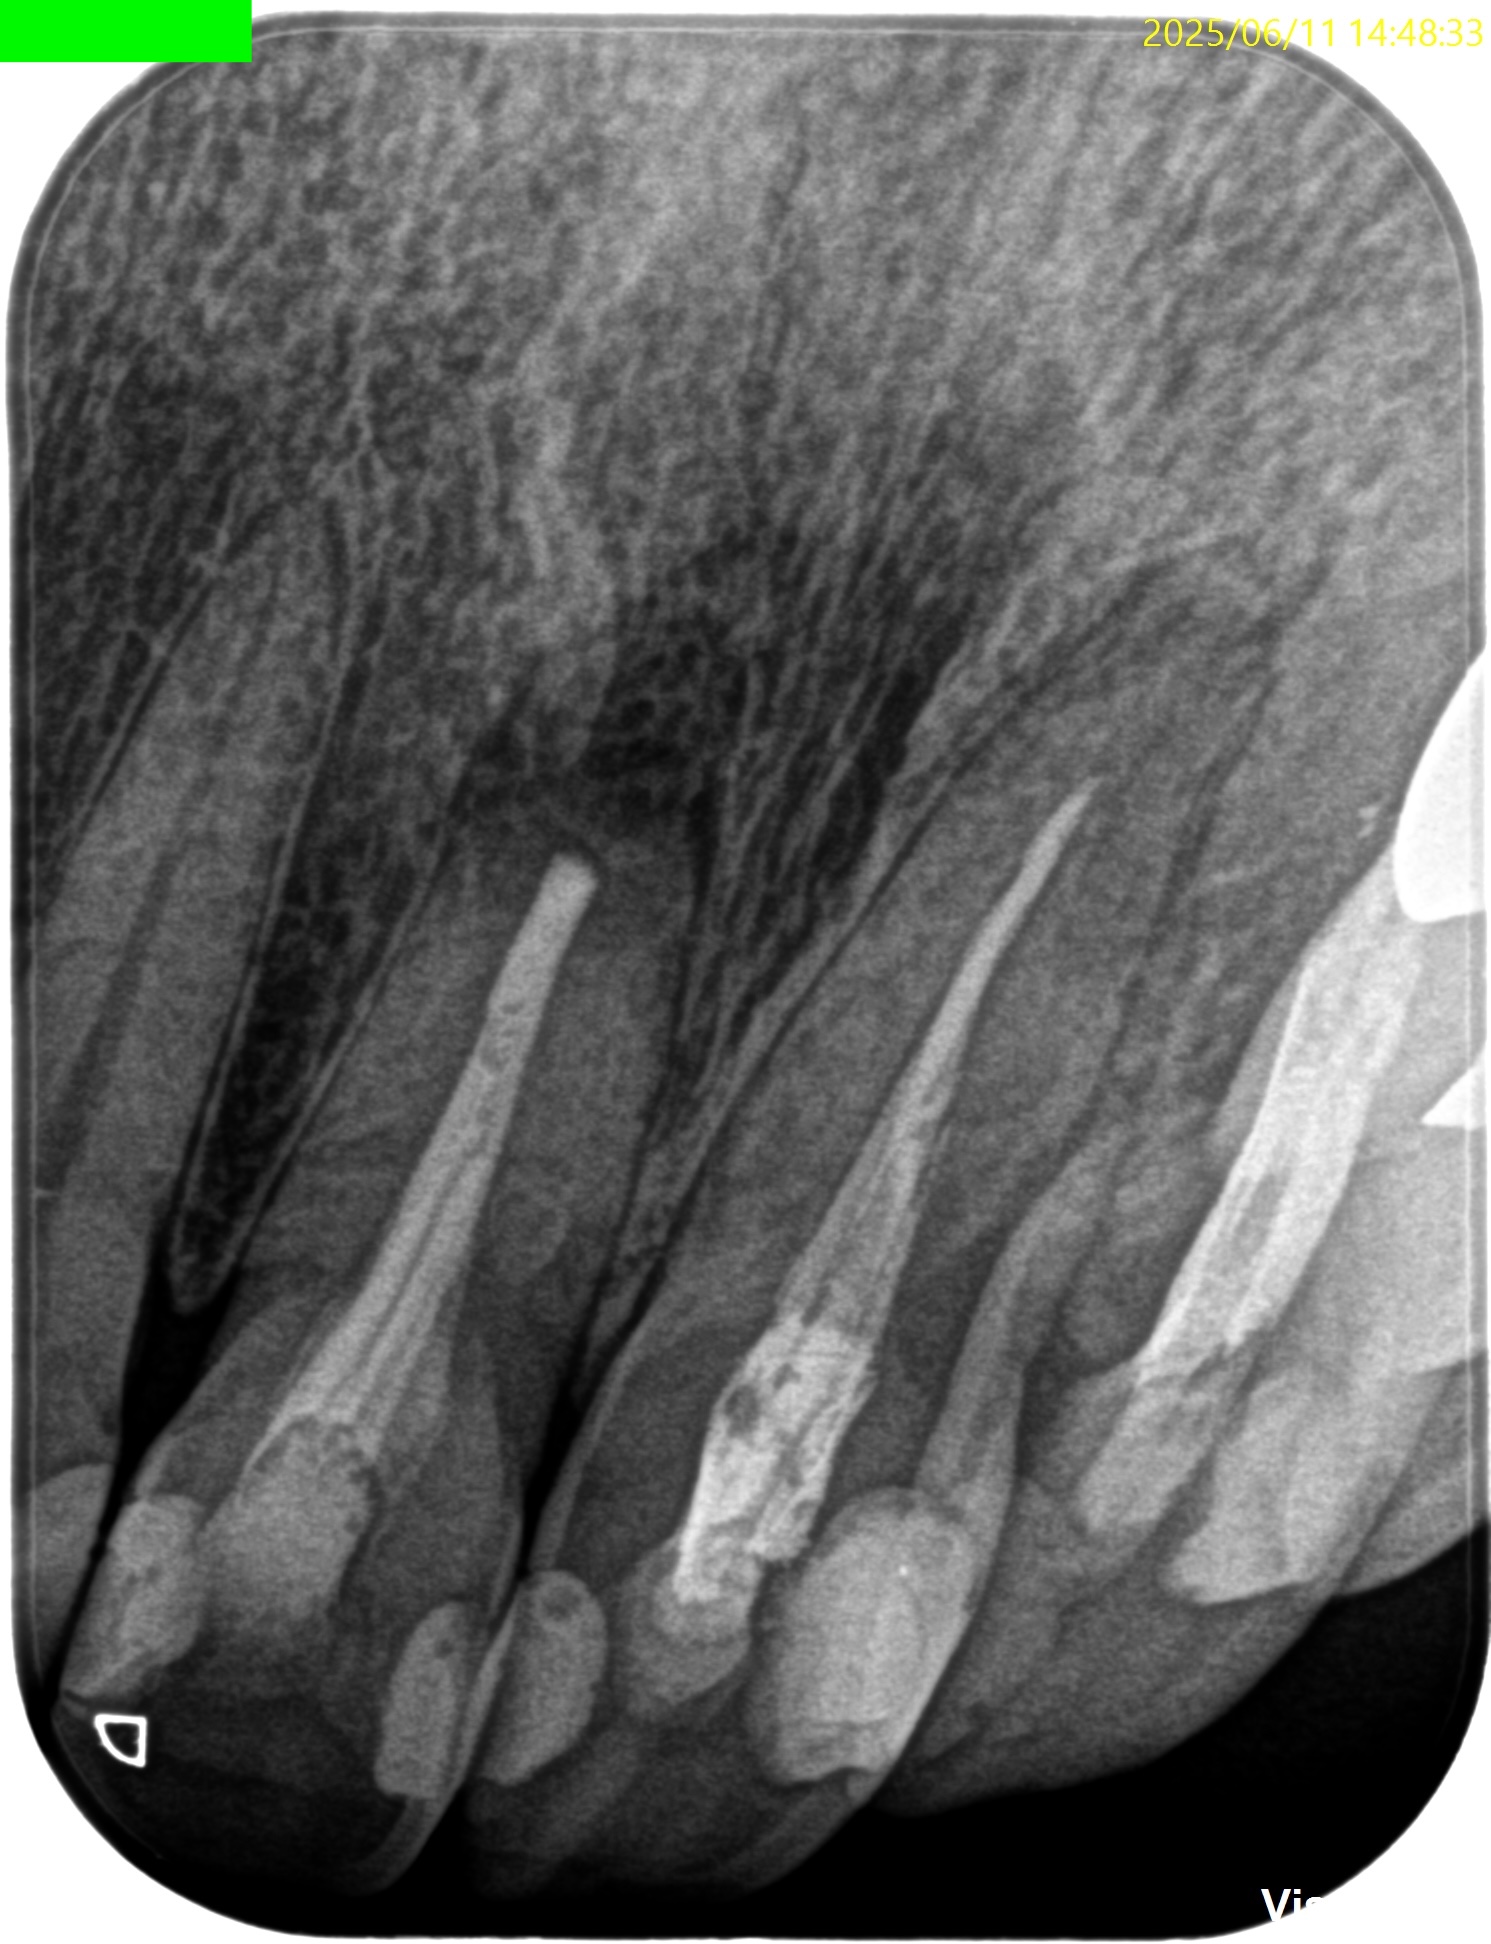

#8 Apicoectomy(2025.6.11)

Submarginal FlapでOpeを行った。

OsteotomyしてApex-3mmを切断した。

逆根管形成した。

逆根管充填した。

PA, CBCTを撮影した。